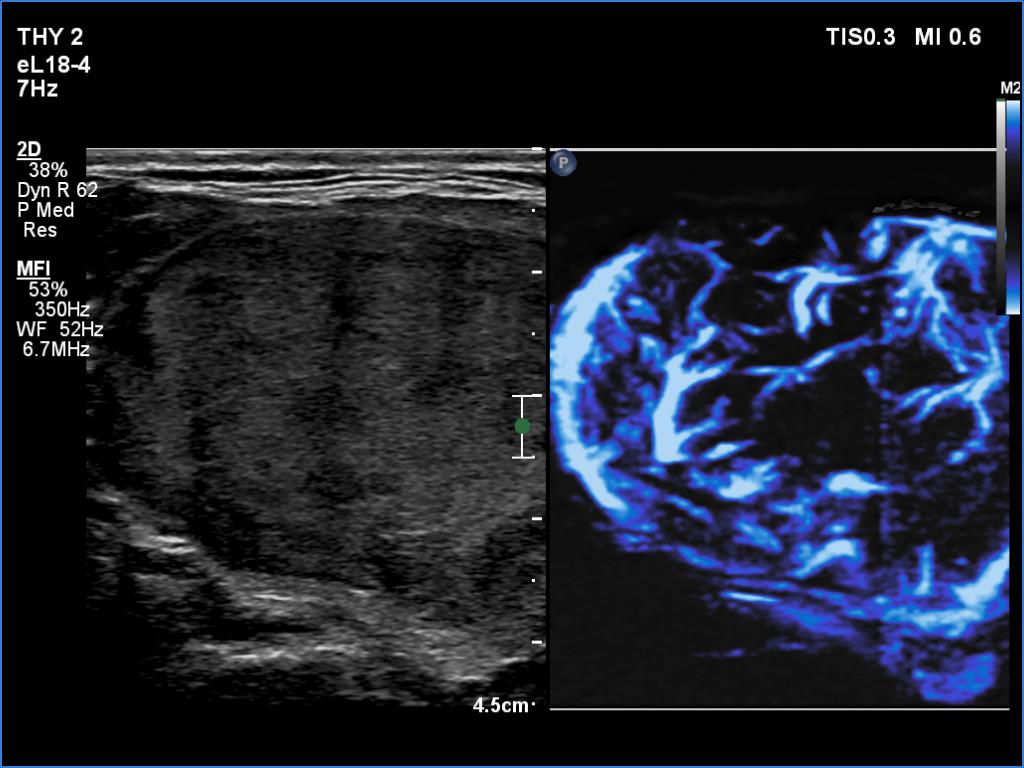

Right lobe, longitudinal scan

Lateral part of the right lobe, transverse scan, microflow imaging. The nodule is rich in vessels.